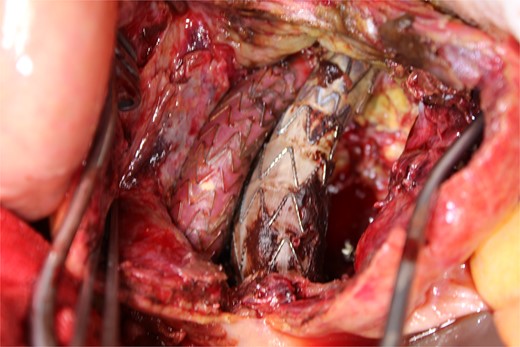

Contrast-enhanced CT revealed an AAA measuring 118 × 107 mm and left retroperitoneal hematoma. One pair of lumbar arteries was enhanced only in the delayed phase (red arrows). Intraoperatively, pulsatile bleeding was observed from the left one of this pair.

This time, he was brought to the emergency department with a chief complaint of abdominal pain. His medical history includes Stage 4–5 chronic kidney disease (CKD), with an estimated glomerular filtration rate (eGFR) of approximately 15 mL/min/1.73 m2, secondary to nephrosclerosis and diabetic nephropathy, as well as persistent atrial fibrillation, which was treated with warfarin. Upon admission, laboratory results revealed a hemoglobin level of 6.2 g/dl and a prothrombin time—international normalized ratio (PT-INR) of 6.05. Contrast-enhanced CT demonstrated an AAA measuring 118 × 107 mm, enlarged from 98 × 94 mm 2 months prior, and left retroperitoneal hematoma. IMA and one pair of lumbar arteries were enhanced only in the delayed phase, but blood flow into the aneurysm was not clearly observed (Fig. 1). Given that the landing zones and overlaps of the stent grafts were satisfactory (Fig. 2) and that no type I or type III endoleaks were identified, a ruptured AAA due to TIIEL from the lumbar artery or IMA was highly suspected. We administered 3000 IU/kg of lyophilized human prothrombin complex concentrate in response to the significant prolongation of PT-INR and proceeded with open surgery for ligation of the feeding artery and aneurysmorrhaphy. Intraoperatively, no pulsation was found on the aneurysm. Incision of the aneurysm revealed a large amount of thrombus, which was removed, and then pulsatile bleeding was identified from a lumbar artery (Fig. 3), the ostium of which was sutured from within the aneurysm. This was consistent with the left lumbar artery of the pair enhanced on the preoperative CT and was suspected to be responsible for the rupture. Oozing was also noted from several other lumbar arteries, which were similarly sutured closed. No leak was observed from the proximal or distal ends, nor from the junctions of the stent grafts, and no damage to the stent grafts was observed (Fig. 4). Following this, aneurysmorrhaphy was performed, and the abdomen was closed. The postoperative course was uneventful. A plain CT on postoperative day (POD) 14 showed a reduction in the aneurysm size with no apparent leaks (Fig. 5). The patient was discharged home on POD 24. Although the preoperative eGFR was 8.8 ml/min/1.73 m2, no postoperative deterioration was observed. It gradually improved back to baseline, and dialysis was not required during the follow-up period.

A photo taken from the caudal side of the patient. No endoleaks other than the type II endoleak were observed.